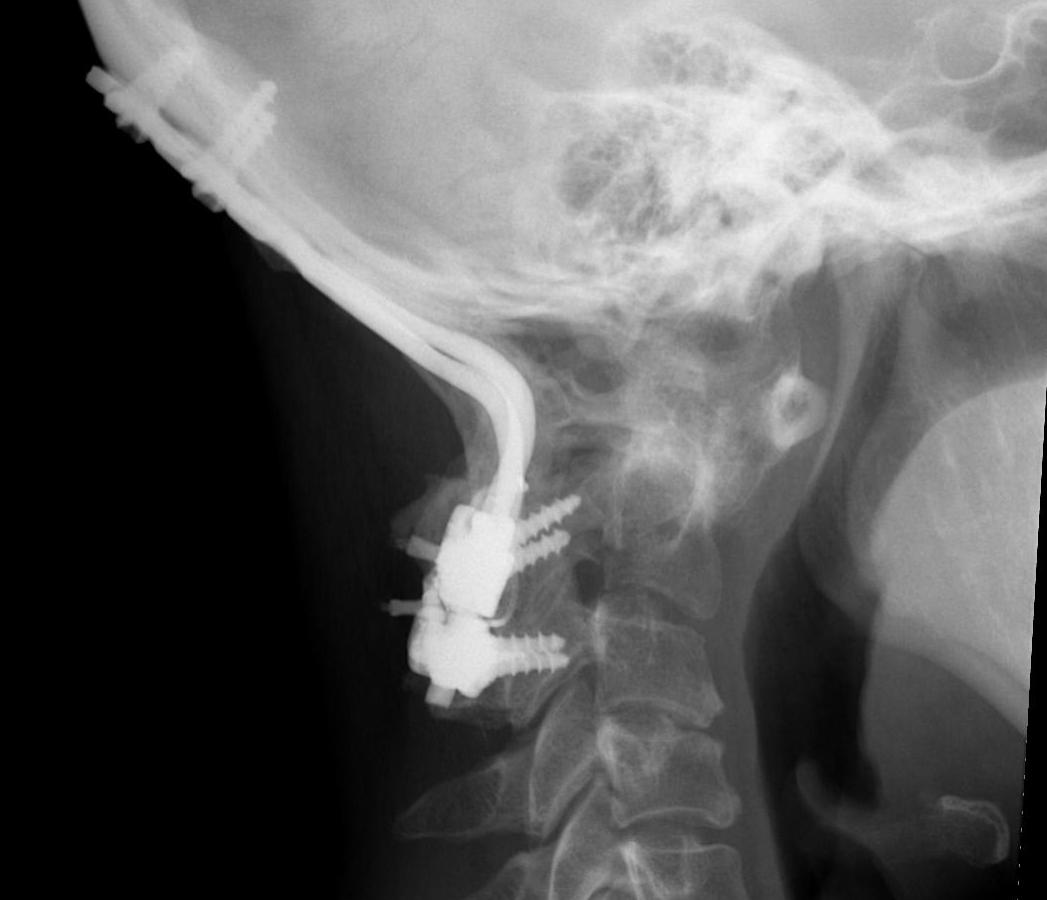

Occipito-cervical fusion

Basilar invagination / Vertical subluxation

Management

Algorithm

1. No symptoms & no cord compression on MRI - observe

2. Cord compression

- occiput to C2 fusion

- +/- C1 laminectomy

- +/- odontoidectomy